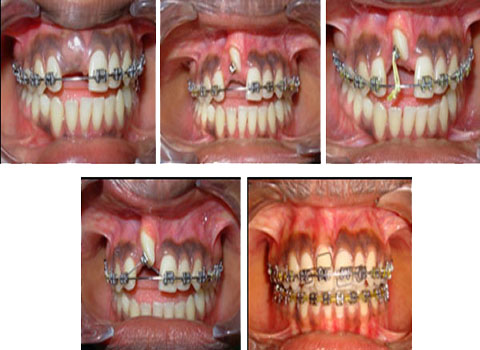

Namman Dental hospital all of your dental needs under one roof and that includes specialists, flexibility in scheduling, inexpensive treatments and much more.

Get yourself treated with some of the best and finest dentists of the city visit our dental hospital.